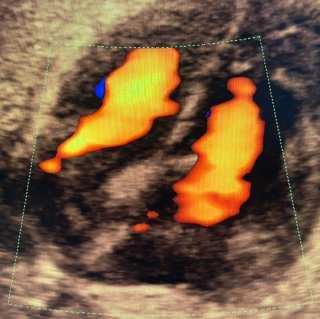

A medida que la medicina avanza, los modelos de atención para el control del embarazo cambiaron de forma signi昀椀cativa a favor de las embarazadas y sus bebés. Estos modelos tienen una relación directa con el uso de las nuevas tecnologías que nos han permitido conocer los mecanismos por los que podemos establecer estrategias de detección oportuna, prevención y tratamiento de las diversas entidades que se presentan en el embarazo.

La implementación de técnicas quirúrgicas novedosas y menos invasivas, el re昀椀namiento de la farmacología, el entendimiento de la bioquímica del cuerpo humano, el desarrollo de la cibernética, la imitación robótica del organismo humano, el estudio de los genes, y otros factores conjuntados, han permitido la obtención de un cúmulo de conocimiento, con resultados alentadores que se ponen al servicio de la raza humana.

EnTuxtlaGutiérrez,apartirdelañode2006,ungrupodeginecó logosenelcualparticipaexitosamenteelGinecólogoDr.Rómu loCristóbalMontesdeOcaRodríguezllevadosporeldeseode mejorar la calidad de la atención del embarazo, realizamos la primera certi昀椀cación en diagnóstico prenatal por la Fundación de Medicina Fetal de Londres, y desde entonces empezamos a aplicar el nuevo modelo de atención del embarazo, elcualledatrascendenciaalaevaluacióndelembarazotemprano, pues se ha podido demostrar en el mundo entero, que estas evaluaciones nos permiten actuar anticipadamente para condicionar un cambio en los niveles de riesgo detectados.

Las evaluaciones del primero y segundo trimestre, ha modi昀椀 enormemente los resultados de los embarazos a nivel mundial, reducien do así las tasas de complicaciones maternas y fetales, derivado de una detección oportuna y tratamiento preventivo para las enfermedades que ponen en peligro al embarazo como son el Parto Pre término, la Preeclampsia, la Diabetes Gestacional, la Hemorragia Obstétrica, así como para las enfermedades fetales que ponen sobre aviso a la familia para la toma de decisiones oportunas como en el caso defectos en el desarrollo susceptibles de ser tratados en la vida fetal, o bien como lo son las cardiopatías fetales que obligan a un nacimiento programado en un centro de atención hospitalaria de alta especialidad.Paralarealizacióndetodasestasdeteccionesyprocedimientosserequieredeunentrenamientoyobtencióndecerti昀椀caciones por la Fundación de Medicina Fetal de Londres, de tal modo que estos procedimientos se realicen con estricto apego a las normas, los cuales ade más son auditados anualmente por la misma institución.

Es por todo esto que te invitamos de manera entusiasta a que te realices esta clase de estudios que te permitirán tener más seguridad en el desarrollo de tu embarazo. Si quieres saber más al respecto, puedes contactarnos en nuestras redes sociales.